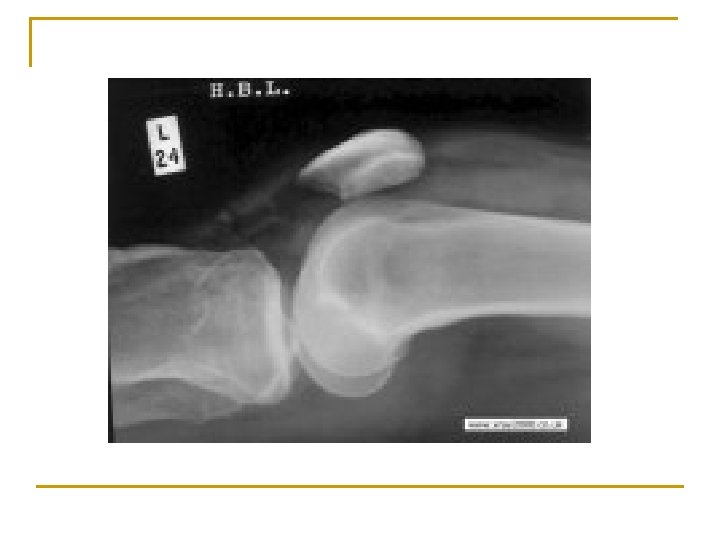

Patellar Tendon Rupture n Cause: Sudden powerful contraction of quads with weight of the body applied to affected leg q n n ***Steroid injections to this area increase likelihood of rupture S/S: Patella moves upward, noticeable defect, and athlete cannot extend knee TX: Conservative: Surgical repair n n NSAIDS ST: X-Ray, MRI